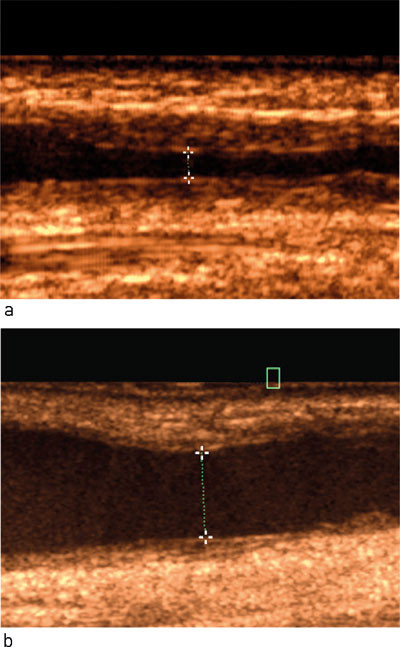

Høy blodstrøm kan føre til utvikling av veggforandringer i venen (intimahyperplasi) som gradvis kan forårsake innsnevring av venen, og ev. en signifikant stenose. Med ultralyddoppler kan en stenose lokaliseres og graderes basert på doppler- og diametermålinger, og blodstrøm i fistelen kan måles og sammenliknes med tidligere verdier (fig 2). Ved påvist signifikant stenose, ofte kombinert med målt synkende blodstrøm i fistelen, foreligger vanligvis indikasjon for snarlig PTA-behandling (fig 3) (4, 9, 27).

Hvis det er punksjonsvansker ved dialysen og det finnes tilgang til ultralydutstyr, kan stikkingen gjøres under direkte ultralydveiledning. I andre situasjoner kan det være ønskelig at fistelens forløp og dybde tydeliggjøres med hudmerking eller tegning (2).

I noen tilfeller kan fistelen være umiddelbart truet. En plutselig «taus» fistel er indikasjon for snarlig undersøkelse, og en fisteltrombose bør behandles med tidlig intervensjon (2, 4). Ultralydundersøkelse som øyeblikkelig hjelp kan da uten forsinkelse kartlegge trombens lokalisasjon og utbredelse (fig 4). Direkte kontakt kan deretter tas med intervensjonsradiolog og/eller karkirurg med tanke på intervensjon, for eksempel trombolytisk behandling kombinert med PTA (28). Det er rapportert at de fleste tromboserte fistler kan reddes med endovaskulær teknikk (4, 27) – (29).